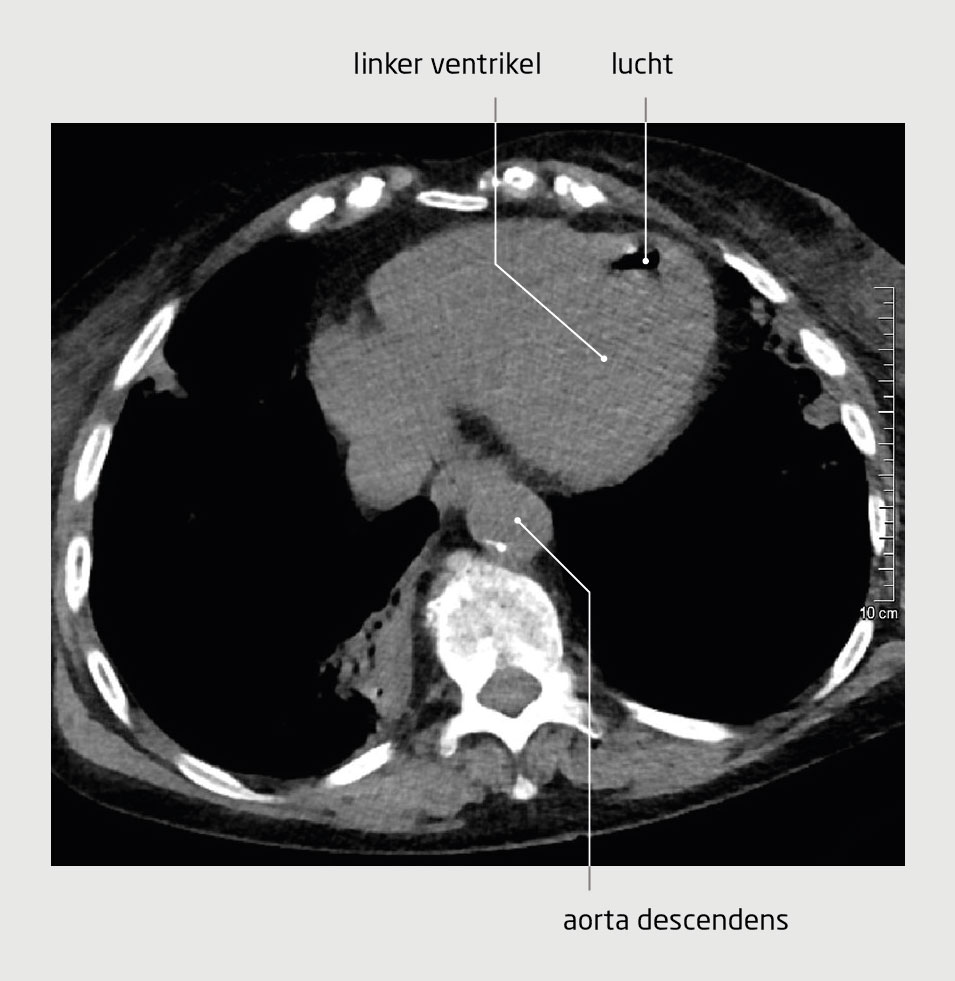

Bij een iatrogene gasembolie is gas aanwezig in de vasculaire structuren, meestal als gevolg van een medische procedure. Zowel arteriële als veneuze gasembolieën kunnen klachten veroorzaken; gasembolieën in de coronairvaten of de cerebrale arteriën kunnen leiden tot een hart- of herseninfarct.

Een 79-jarige vrouw onderging een CT-geleide longbiopsie. Enkele minuten later ontwikkelde ze neurologische klachten. Na toediening van zuurstof verbeterde het klinisch beeld aanvankelijk, maar later verslechterde het opnieuw. Op basis van het klinisch beeld werd de werkdiagnose ‘luchtembolie’ gesteld. De patiënte werd behandeld met hyperbare zuurstoftherapie. Daarna herstelde ze volledig.